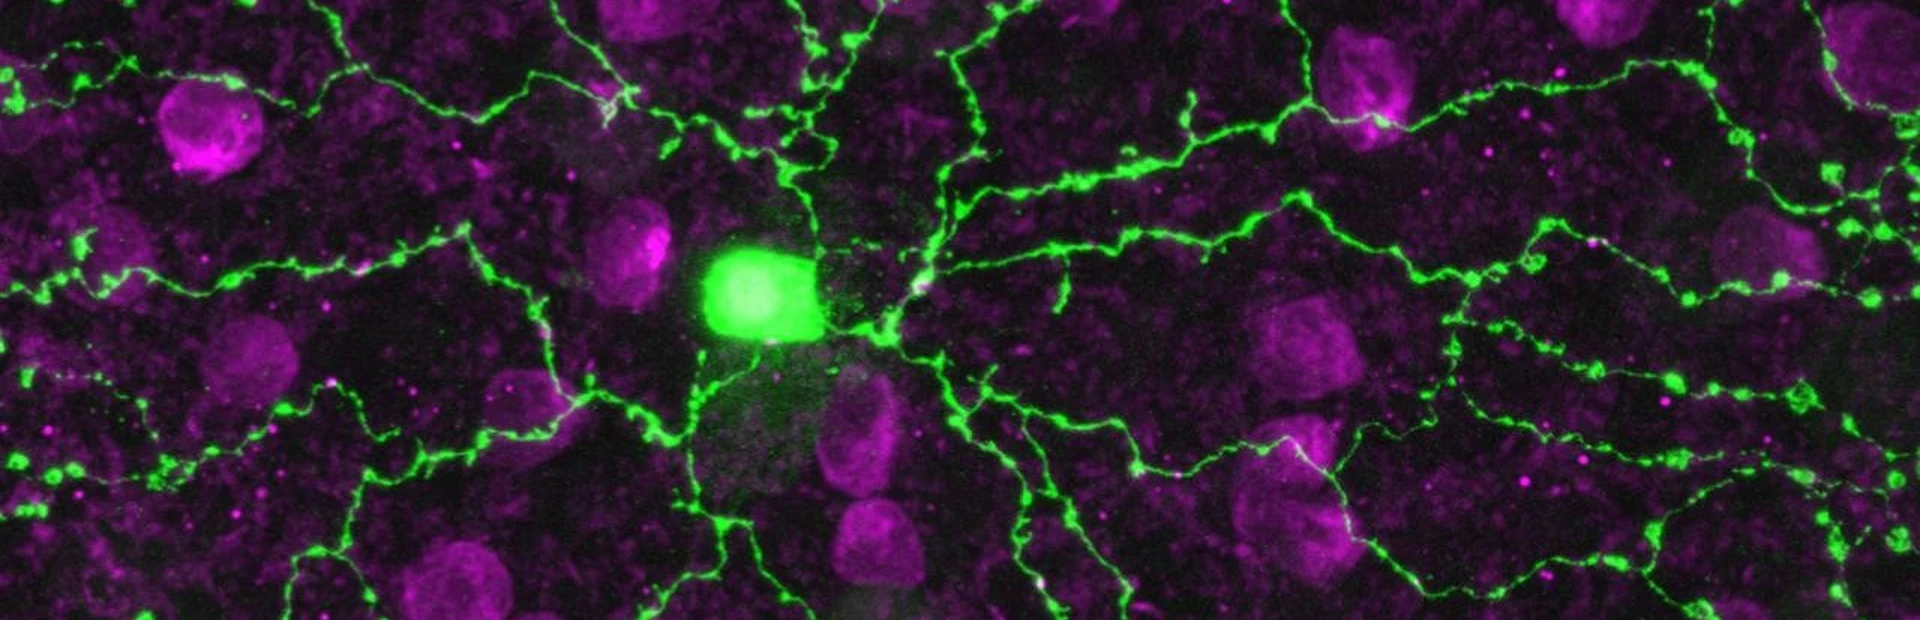

Enter Botond Roska, a neurobiologist and principal investigator at the Novartis-affiliated Friedrich Miescher Institute for Biomedical Research. His group discovered that FRMD7 mutations wreak havoc by sabotaging exquisite retinal cells called starbursts (above). Specifically, the mutations interfere with the cells’ ability to decode sideways movement. This finding, published in Neuron, provides critical insight for understanding and potentially treating nystagmus.

It’s easy to see how the starburst cell got its name. Many arms radiate from a central body. And these projections play a critical function, connecting with other cells in a neural circuit that processes vision. Starburst cells are known to be essential for deciphering and transmitting information about movement in all directions. Given this role, it wasn’t surprising for starburst cells to be implicated in nystagmus. But, there was something peculiar about the starburst cells in the genetically-modified mice.

Main image: This starburst cell (in green) looks healthy, but its faulty cellular contacts underlie the debilitating retinal disease nystagmus. Image by Botond Roska/FMI